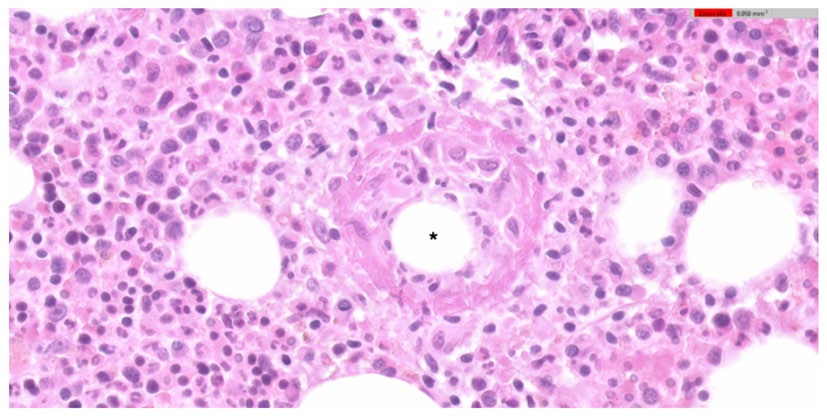

A 71-year-old man presented to the emergency department with 3 weeks of fever, asthenia and night sweats. The initial laboratory results showed mild anaemia, thrombocytopenia and elevated C-reactive protein, with normal liver enzymes. The remaining initial study was unremarkable. Due to haematologic abnormalities, a bone marrow biopsy was performed, revealing multiple ring epithelioid granulomas, consisting of a central lipid vacuole surrounded by epithelioid cells and some neutrophils. These findings, although not pathognomonic, favoured the diagnosis of Q fever with isolated bone marrow involvement. The diagnosis was later confirmed by seroconversion and exclusion of other causes for this histopathologic finding. The patient was treated with doxycycline for fourteen days with a good response and no evidence of the disease after six months.